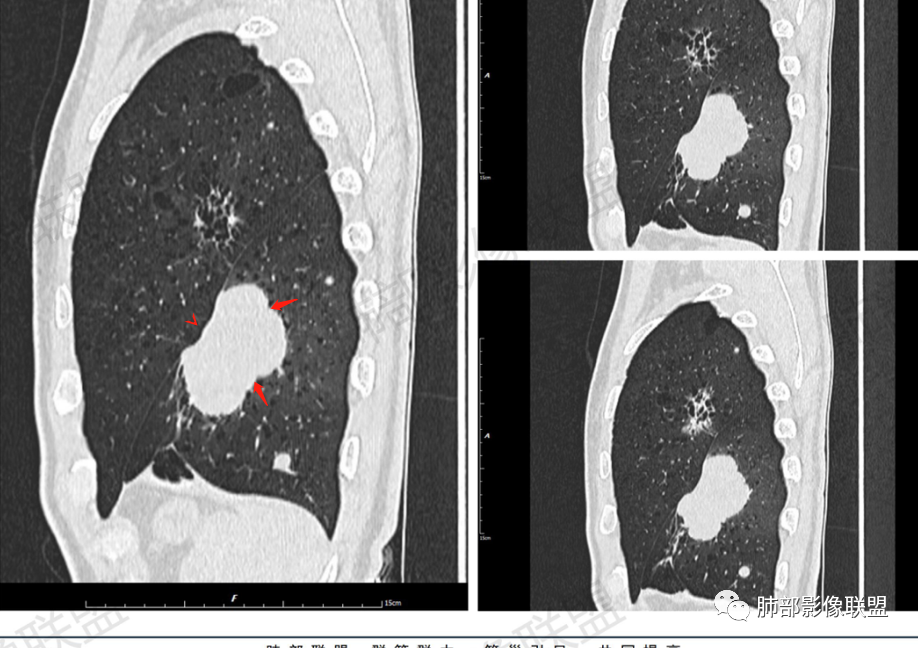

一切∮随缘:左肺下叶不规则肿块,边缘光滑,平直,局部彭隆,分叶,近端支气管堵塞,远端与胸膜相贴,平扫密度尚均匀,增强后不均匀强化,内部可见低密度坏死,胸膜下多发肺气肿,伴双肺散在光滑小结节,实验室肿瘤标志物高,考虑恶性:神经内分泌癌(大细胞),腺癌,鳞癌。

琦遇:恶性没有问题,肺气肿底子、病灶分叶、少许毛刺、叶间胸膜凹陷、部分边缘可见清晰的GGO、胸膜牵拉凹陷、局部胸水、近端支气管截断、部分支气管被推移、占位效应明显、强化特点为不均匀强化、内部有少许沼泽样低强化区,强化部分轻中强化为主、余肺可见转移性结节、左肺上叶似为囊腔型腺癌一枚,肿瘤标志物提示非小、神经内分泌,综合分析考虑大神泌、腺癌、腺鳞癌、鳞癌  同时左肺上叶囊腔型腺癌  肺转移

飞鹰行动:中年人,男性,胸疼入院,左肺下叶占位,张力较高,边界可见分叶,局部可见明显收缩性改变,增强病灶内部有延迟强化表现,考虑恶性病变,大细胞癌伴肺内转移或者囊腔样腺癌伴转移。

蕊:中老年男性,吸烟史,肺气肿背景,左肺上叶类圆形肿块影,边界清晰,边缘凹凸不平,有分叶,支气管进入阻断,临近胸膜栽赃,整体病灶膨隆,局部周围可以清晰ggo,临近叶间裂内凹,轻度强化,并可见多个低密度区,坏死可能,界线不清;肺内多结节,边缘光滑,考虑恶性伴转移,鳞癌、腺癌

傅昌瑜:中老年男性,肺气肿背景,右胸背疼痛1周。CEA、NSE、CYFRA—211升高。左上肺混合磨玻璃结节,内见较多空泡和扩张支气管。左下肺胸膜下肿块,边缘较光滑,深分叶,似有血管进入,与支气管关系不清,内见不均匀强化,见沼泽地样坏死,有胸膜栽赃。另两肺多发圆形小结节。考虑恶性并肺内转移,多原发可能性大,左上肺腺癌,左下肺病理难以判断,小细胞癌?鳞癌?

小锁:中老年男性,肺气肿背景,右胸背疼痛1周。CEA、NSE、CYFRA—211升高。左上肺混合磨玻璃结节,边界清楚,内见较多空泡。左下肺肿块,边缘清楚,深分叶,有血管和支气管进入,胸膜凹陷。另两肺多发圆形小结节。考虑双发原位癌,左上肺腺癌,左下肺大神泌或腺鳞癌可能,肺内转移。

蓝天白云:中年男性,肺气肿背景,左肺下叶肿块,边缘膨隆,有分叶,内有湖泊样坏死,有轻中度强化,局部胸膜栽赃,收缩力不强,周围见肺气肿征象。左肺上叶混合磨玻璃影,边界清楚,考虑都是恶性,左上肺iac,左下肺腺鳞癌,或大细胞肺癌可能。两肺多发结节,考虑转移

毛勤香:老年男性,肺气肿背景,左肺下叶肿块,分叶,边缘光滑,土豆块样,细支气管闭塞,增强轻度不均匀强化,似有坏死,左肺另见多发结节,淋巴结未见明显肿大,恶性确定,吸烟史,鳞癌破坏力强,侵袭力差,多原发的一般很少多于3个,故排后,首先考虑神经内分泌癌,局部血管穿行,鉴别淋巴瘤

周太狼:中年男性,吸烟、高血压史,肿瘤指标升高,肺气肿背景下,左肺下叶肿块影,分叶、膨隆、未跨叶裂,支气管截断,不均匀强化。另双肺多发结节及磨玻璃影,左肺上叶混合磨玻璃,内可见多发空泡影。整体考虑恶性,肺癌伴肺内转移,左下肺鳞癌?神经内分泌癌?左肺上叶囊腔腺癌?